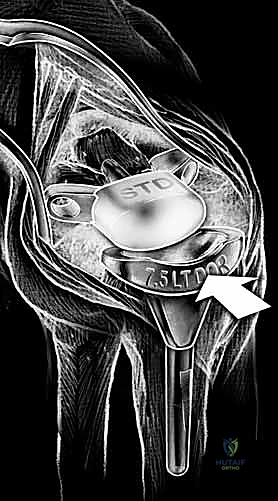

6. تثبيت المفصل الصناعي النهائي

يتكون المفصل الصناعي من جزأين رئيسيين: الجذع الكعبري (الذي يُزرع في عظمة الكعبرة في الساعد) والجذع الرسغي (الذي يُزرع في عظمة المشط الثالثة في اليد). يتم تثبيت هذه الأجزاء إما باستخدام الإسمنت العظمي الطبي، أو عن طريق الانحشار الميكانيكي الدقيق (Press-fit) الذي يسمح بنمو العظم داخل المفصل الصناعي. بين هذين الجزأين المعدنيين، توضع قطعة بلاستيكية عالية الجودة تعمل كغضروف صناعي يسمح بالحركة السلسة.